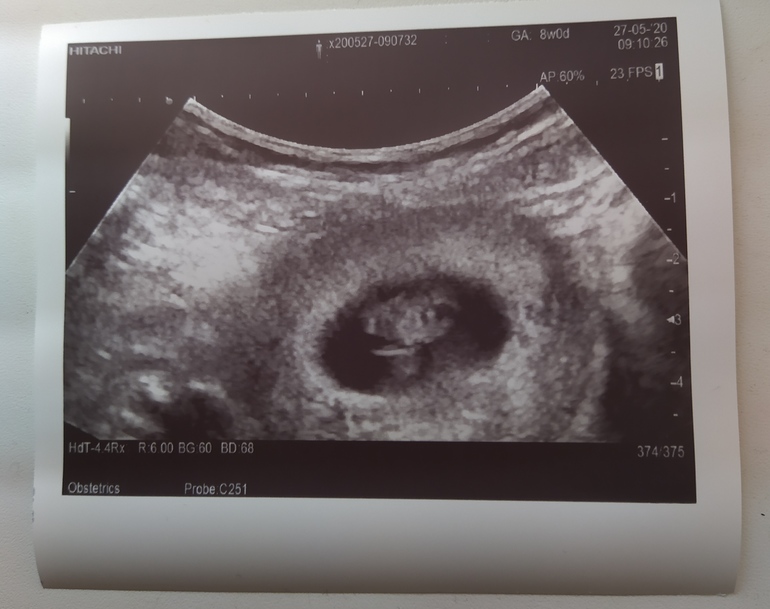

УЗИ на раннем сроке: что можно увидеть на 8 неделе беременности

На форуме 8 недель беременности тема первого УЗИ — настоящий хит. Будущие мамы делятся своими переживаниями, радостями и, конечно же, снимками своих крошечных «горошинок». «Я как будто побывала в космосе, — восторженно пишет одна из участниц. — Только вместо звезд и планет увидела своего малыша!»

И действительно, первое УЗИ на 8 неделе беременности — это настоящее путешествие в неизведанное. Многие женщины на форуме 8 недель беременности признаются, что испытывали смешанные чувства перед процедурой. «Я волновалась так, будто шла на экзамен, — делится одна из будущих мам. — Только вместо учебников штудировала форумы и статьи о раннем УЗИ».

Что же можно разглядеть на экране монитора?

Форум 8 недель беременности пестрит обсуждениями того, что же удалось увидеть на УЗИ. Кто-то в восторге от того, что смог разглядеть крошечное сердечко, бьющееся со скоростью 160 ударов в минуту. «Это было похоже на крошечный моторчик!», — восклицает одна из участниц. Другие делятся впечатлениями от вида эмбриона, который на этом сроке уже напоминает крошечного человечка.

Интересно, что многие женщины на форуме 8 недель беременности отмечают, как быстро растет малыш. «Когда врач сказал, что эмбрион уже размером с малину, я не поверила своим ушам, — пишет одна из будущих мам. — Кажется, еще вчера он был с маковое зернышко!»

Снимок на память: первое фото малыша

Тема первого снимка УЗИ — еще один горячий топик на форуме 8 недель беременности. Будущие мамы делятся своими «фотосессиями», обсуждают, на кого похож малыш и даже устраивают конкурсы на самое четкое изображение. «Я теперь как папарацци, — признается одна из участниц. — Везде ношу с собой снимок УЗИ и показываю всем подряд. Кажется, даже кассир в супермаркете уже в курсе, что у меня будет малыш!»

Многие женщины на форуме 8 недель беременности рассказывают, как творчески подошли к хранению первого снимка УЗИ. Кто-то вставил его в рамку и повесил на стену, кто-то сделал специальный альбом, а кто-то даже заказал футболку с изображением своего эмбриона. «Я теперь как ходячая выставка, — шутит одна из будущих мам. — Ношу своего малыша не только под сердцем, но и на груди!»

Многие женщины на форуме 8 недель беременности отмечают, что после УЗИ их беременность стала казаться более реальной. «До этого момента я как будто жила в каком-то сне, — признается одна из будущих мам. — А теперь, увидев малыша на экране, я наконец-то поверила, что скоро стану мамой. Это и страшно, и восхитительно одновременно!»